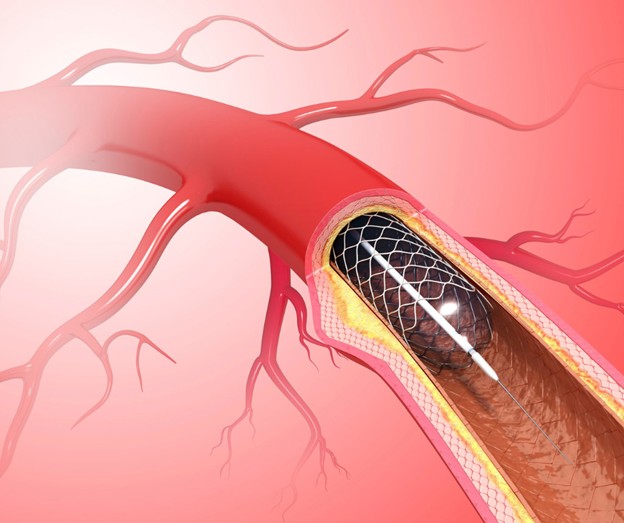

القسطرة القلبية هي إجراء طبي يتم خلاله إدخال أنبوب رفيع ومرن يُسمى “القسطرة” عبر أحد الأوعية الدموية، غالبًا من خلال الشريان الفخذي في منطقة الفخذ أو الشريان الكعبري في اليد، ثم يتم توجيه هذا الأنبوب إلى شرايين القلب باستخدام الأشعة السينية. يُعد هذا الإجراء أحد أهم الوسائل الطبية لتشخيص أمراض القلب بدقة عالية، كما يستخدم أيضًا في العلاج، مما يجعله واحدًا من الإجراءات الأكثر شيوعًا في العالم لعلاج الانسدادات الشريانية.

وليس ذلك فحسب، بل تُعد القسطرة القلبية اليوم واحدة من أهم طرق العلاج غير الجراحي، حيث يمكن للطبيب خلال نفس الإجراء فتح الشريان المتضيق باستخدام بالون صغير، أو تركيب دعامة تحافظ على سريان الدم. لذلك أصبحت القسطرة القلبية حلًا مثاليًا للعديد من المرضى، خاصةً أولئك الذين يريدون تجنب العمليات الجراحية الكبرى أو لديهم مخاطر عالية تمنعهم من الخضوع لها. وباختصار، فإن القسطرة القلبية ليست فقط وسيلة تشخيص، بل أيضًا أداة علاجية تنقذ حياة الملايين حول العالم سنويًا.

إذا كانت القسطرة تشخيصية فقط، يتم تصوير الشرايين بزاويا مختلفة، ثم تُسحب القسطرة ويُغلق مكان الدخول بضغط مباشر أو باستخدام جهاز إغلاق خاص. أما إذا كانت القسطرة علاجية، فقد يقوم الطبيب بتمرير بالون صغير داخل الشريان المتضيق ونفخه لفتحه، أو تركيب دعامة معدنية تحافظ على مرور الدم بشكل طبيعي.

ويُطلق عليها “التدخل التاجي عبر القسطرة”. يتم خلالها علاج الانسدادات الشريانية من خلال إدخال بالون صغير داخل الشريان المتضيق ونفخه لإعادة فتحه. بعد ذلك تُزرع دعامة (Stent) تساعد في إبقاء الشريان مفتوحًا ومنع انسداده مرة أخرى. وهناك أنواع حديثة من الدعامات تطلق أدوية تمنع رجوع التضيق.